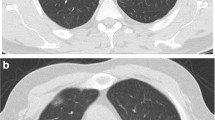

CT images were prospectively interpreted by one of two radiologists with 2 and 5 years of experience, taking into consideration the available clinical information and the result of the nasopharyngeal swab if available at the time of CT interpretation (N = 71). Signs of COVID-19 infection included ground glass opacities in a multifocal peripheral distribution, crazy paving, vascular dilation, subpleural bands and consolidations (Fig. 1) [7, 21,22,23,24,25,26,27,28,29,30]. A semi-quantitative evaluation of parenchymal involvement was also performed. A categorical assessment scheme was used to conclude the study regarding the probability of COVID-19 infection as follows: 1: normal exam, 2: other infection is more likely, 3: indeterminate for COVID-19, moderate probability, 4: highly suggestive of COVID-19, 5: typical findings for COVID. In this paper, scores ≥ 3 were considered positive for COVID-19 [31].